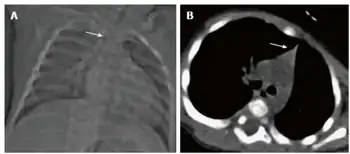

| Thymic hypoplasia in infant with primary immunodeficiency- a) Small thymus b) triangular configuration of thymus | |

Thymic hypoplasia is a condition where the thymus is underdeveloped or involuted.[1]